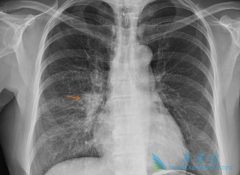

一般肺癌发现都比较晚,很多病人和家属都不敢信息,因为好好的一个人就被确诊为肺癌晚期了,实在难以接受,今天小编给大家讲下 肺癌有什么症状 ?肺癌疼痛,声音嘶哑,面、颈部水肿,气促、胸腔积液等都是常见的肺癌晚期症状。疼痛是最常见的肺癌晚期症 ...

肺癌的死亡率非常高,因此人们都非常担心会患上肺癌这种疾病,肺癌的发生会给患者带来的是无尽的痛苦,但是如果我们能够及时的发现肺癌疾病的症状的话,我们就可以及时的进行治疗,减少伤害,下面我们就一起了解一下 肺癌早期的症状 有哪些吧!   非常 ...

肺癌始终位居恶性肿瘤的发病率和死亡率的第一位,谈及肺癌,很多人首先会想到, 肺癌的症状 有咳嗽,导致肺癌最常见的原因是吸烟,那么,除了这些以外,你应该对肺癌有更深的了解。第一,刺激性干咳,肺癌最早出现的症状时刺激性干咳,常常在遇到冷空气 ...